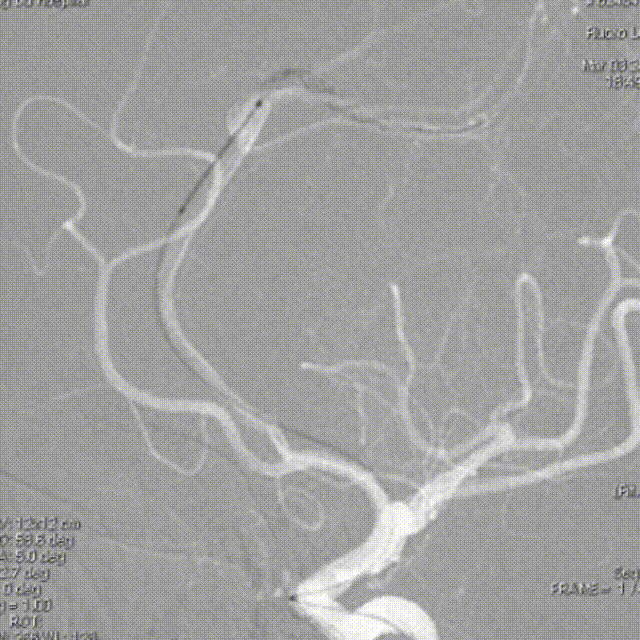

微导丝超选

支架输送到位

支架头中端释放

支架中近端释放

支架完全释放,回收导丝

支架内按摩

微导丝再次超选

支架二次头端和中段释放

支架二次近端释放

支架再次调整完全释放及推送回收导丝

术后正侧位造影显示支架贴壁良好,血管重塑满意,血流改善明显。